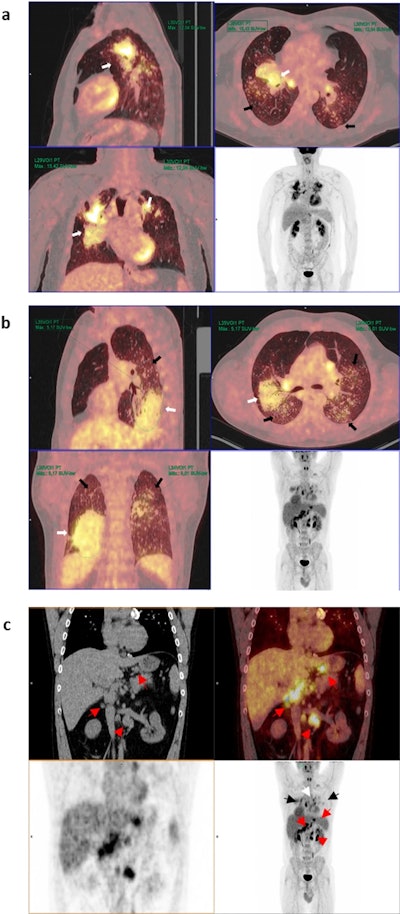

Representative PET/CT images from patients with: (a) high and (b) low SUVmax values and (c) hypermetabolic lymphadenopathy in other extrathoracic areas. (a) Maximum intensity projection (MIP) PET images (bottom right) and sagittal, axial and coronal and PET/CT images of a patient with bilateral pulmonary heterogeneous condensations (white arrows) showing intense metabolic activity up to an SUVmax of 15.42 in the right upper lobe, as well as scattered millimetric nodules (black arrows). (b) MIP PET images and in the sagittal, axial and coronal PET/CT images showing bilateral pulmonary condensations, which are larger on the right side (white arrows), and numerous bilateral millimeter-sized nodules (black arrows). Slight diffuse and heterogeneous increased uptake (up to an SUVmax of 5.17) is observed, even in areas of apparently healthy lung parenchyma. (c) PET, CT, and PET/CT images in coronal and MIP sections in which, in addition to bilateral pulmonary (black arrows) and mediastinal (white arrow) involvement, multiple abdominal lymphadenopathies are observed in the celiac space, gastrohepatic ligament, and retroperitoneum (red arrows), even below the renal artery (red arrowhead).Scientific Reports

According to the analysis, the average maximum standardized uptake value (SUVmax) of large opacities was 6.32 ± 3. All of the patients demonstrated hypermetabolic mediastinal lymphadenopathies, and 88.2% of the patients also demonstrated extrathoracic lymphadenopathies.